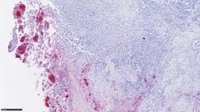

En los últimos años se han desarrollado condiciones de cultivo que permiten mantener 'in vitro' células madre de diferentes órganos, dando lugar a estructuras que se asemejan a tejidos humanos en miniatura que son los llamados organoides o miniórganos.

Asimismo, este sistema también se ha utilizado para extraer de pacientes con cáncer de hígado células tumorales y cultivarlas en el laboratorio para conseguir "minitumores de hígado fuera del paciente".

"Esto sirve para identificar nuevos genes implicados en su desarrollo, para probar nuevos fármacos o ver cuáles son los que van a ir mejor a cada paciente", ha explicado.